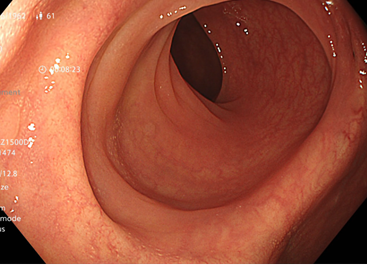

Kết quả nội soi đại tràng: có 3 polyp đại tràng (Paris Is, Kudo IIIL) (đã được cắt polyp qua nội soi), đại tràng sigmoid đã cắt một phần, tổn thương lồi đại trực tràng dạng polyp không cuống, ranh giới rõ, bề mặt màu hồng, có nhiều polyp có lớp nhầy ở trên bề mặt và thấy có hình ảnh da gà xung quanh tổn thương. Trên hình ảnh M-NBI thấy các tổn thương có các tuyến giãn nhẹ nhưng còn đều, mạch máu giãn nhẹ, chưa có biến đổi hình dạng --> đã tiến hành sinh thiết

Hình 2: Hình ảnh nội soi đại tràng

Tổn thương trên nội soi là hình ảnh các tổn thương lồi tại đại trực tràng dạng polyp không cuống, ranh giới rõ, bề mặt màu hồng, có nhiều polyp có lớp nhầy ở trên bề mặt. Chúng tôi nghĩ đến đây là hình ảnh của đa polyp mũ đại tràng mặc dù kết quả mô bệnh học chỉ kết luận là tổn thương viêm trợt mạn tính đang hoạt động, tạo hình ảnh giả polyp. Do trước đó cô ấy đã trải qua nhiều phương pháp điều trị theo hướng viêm ruột như kháng sinh Tinidazol, Levofloxacin, mesalazine… nhưng tình trạng đại tiện nhiều lần không được cải thiện, cùng với đó chúng tôi ghi nhận thấy có sự hiện diện của vi khuẩn H.pylori ở dạ dày. Vì vậy chúng tôi đã quyết định điều trị diệt trừ vi khuẩn H.pylori bằng phác đồ 4 thuốc: Tetracyclin 2g/ngày, Tinidazol 1,5g/ngày, Esomeprazol 80 mg/ngày, Bismuth 480 mg/ngày, thời gian điều trị là 2 tuần.